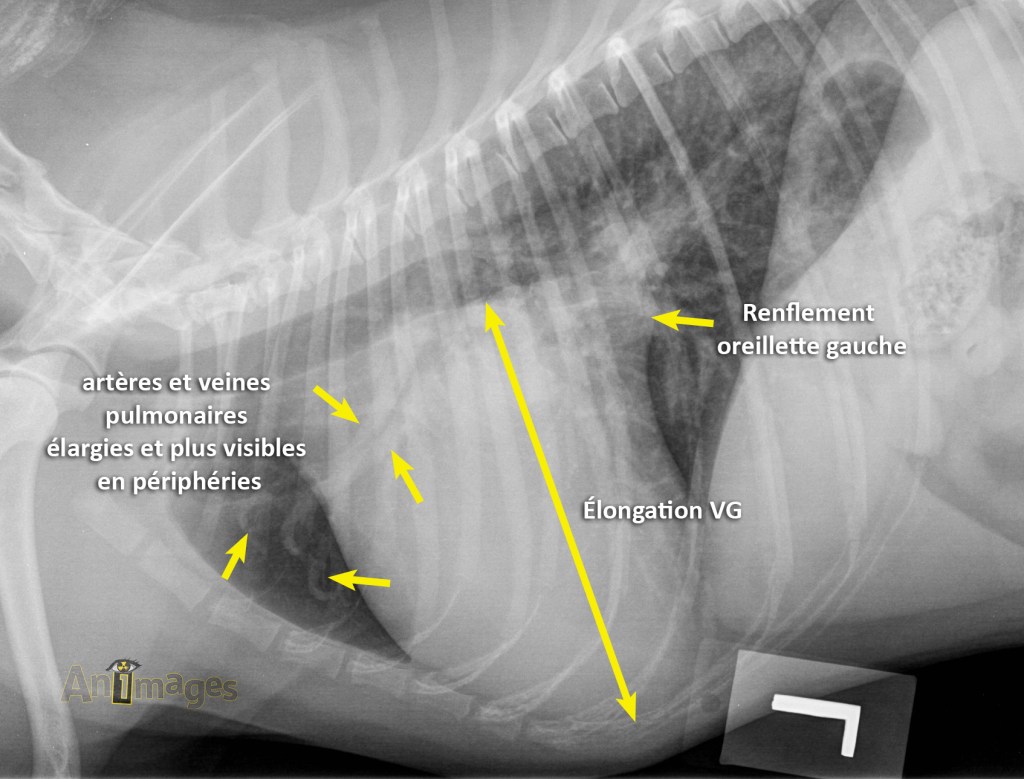

Voici un chat domestique de 7 ans mâle castré présenté pour suivi de sa condition cardiaque. En plus de l’évaluation de la silhouette cardiaque, un examen attentif des vaisseaux pulmonaires crâniaux et caudaux est requis.

En comparant les deux projections, on peut apprécier que la dorsoventrale met davantage en relief les vaisseaux des lobes caudaux (flèches jaunes). On peut aussi y voir que l’extrémité caudale des lobes pulmonaires s’étend plus caudalement en DV (flèches noires), confirmant leur plus grande insufflation.

La DV est également idéale pour l’évaluation cardiaque, puisque le cœur bascule moins et sa position dans le thorax est plus constante d’un animal à l’autre, facilitant la détection de changement de forme ou de taille.